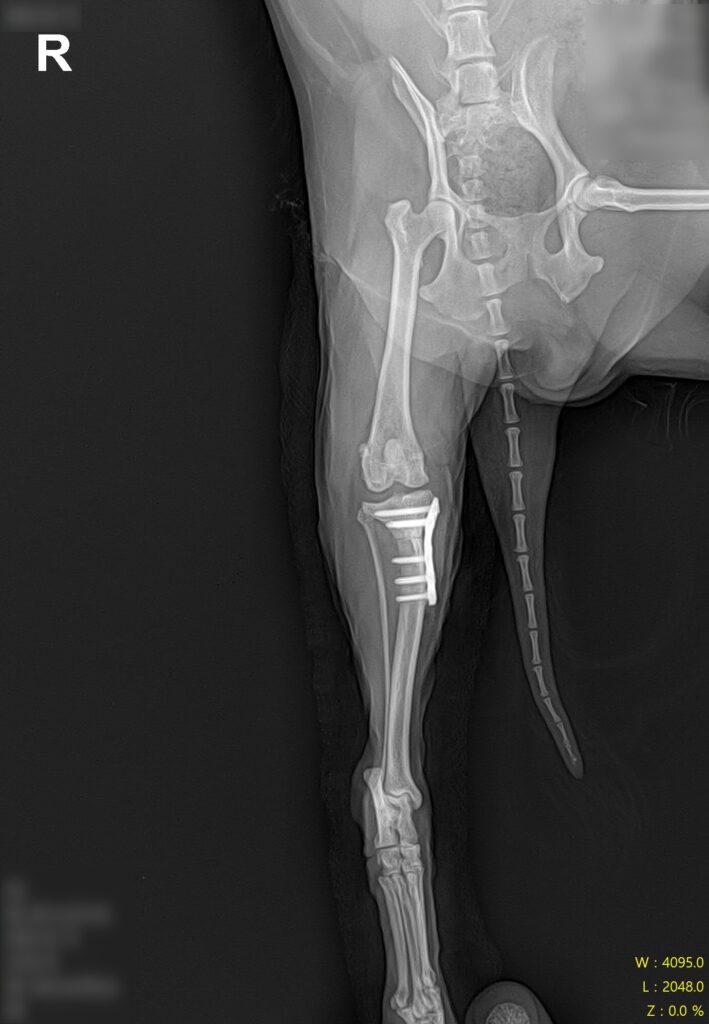

수술 전 방사선 검사 / 출처: 라온동물메디컬센터

정형학적 검사와 방사선 영상 검사를 진행한 결과, 우측 슬관절의 불안정성과 함께 전방십자인대 단열(CCL rupture) 소견이 확인되었습니다. 기존 슬개골 수술 부위의 임플란트 상태는 양호했으나, 슬관절 주변으로 골관절염 진행과 관절 삼출액 소견이 동반되어 있었습니다.

십자인대 수술 후 방사선 검사 사진 / 출처: 라온동물메디컬센터

수술 후에는 통증 관리, 체중 부하 단계 조절, 관절 가동 범위 관리, 근육 회복을 위한 재활 관리를 함께 진행하며 회복 과정을 면밀히 모니터링했습니다. 단계적인 재활 프로그램을 통해 근육을 회복시켜 나간 결과, 봄이는 정상 보행을 회복하여 퇴원하였습니다.